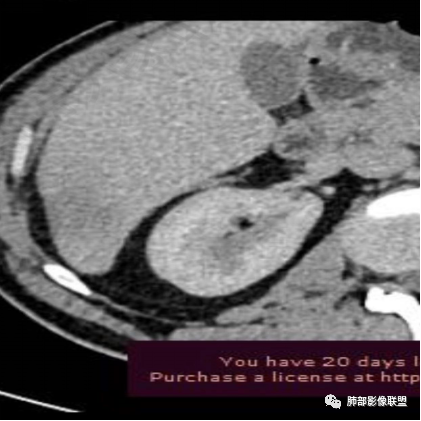

平扫图像

增强图像

肝脏病变明确,是轻度强化,延迟强化特点,边缘模糊,有轻微的包膜挛缩。